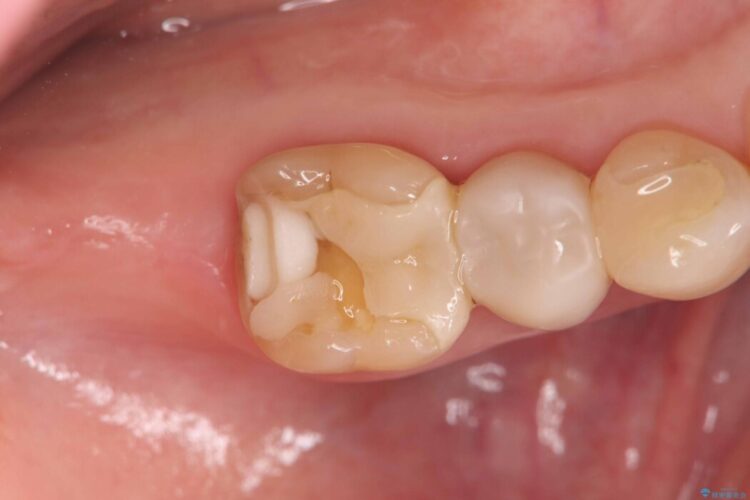

詰め物内部の虫歯治療、隠れた根管の発見

詰め物内部の虫歯治療、隠れた根管の発見 ビフォー 詰め物内部の虫歯治療、隠れた根管の発見 アフター

奥歯の詰め物が取れたとご来院された患者様です。